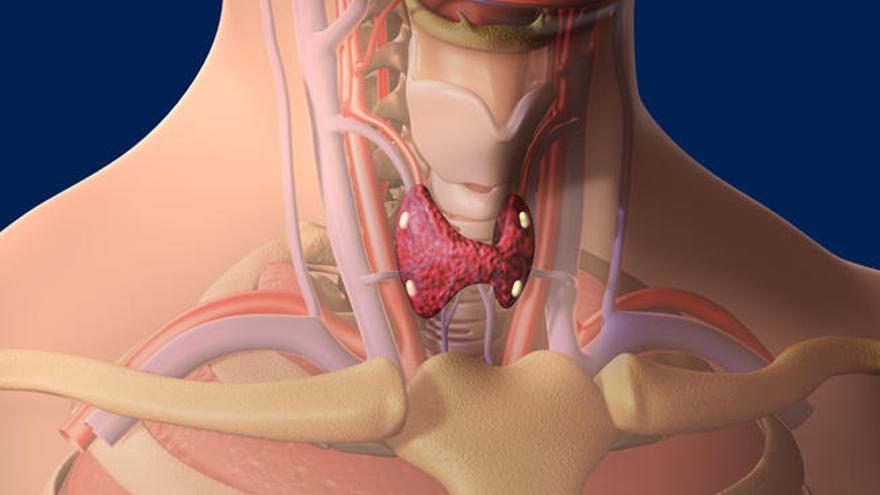

El síndrome de Cowden, la enfermedad que decía padecer Paco Sanz -el valenciano detenido por estafa- es una enfermedad de origen genético. Se caracteriza por la aparición en diferentes órganos de una serie de tumores benignos que se llaman hamartomas. Las principales localizaciones son piel, tiroides, mama, tracto gastrointestinal, cerebro y útero. Los pacientes están predispuestos a presentar tumores malignos con mayor frecuencia que la población general, principalmente cáncer de mama, cáncer de tiroides y de endometrio. Por ello el diagnóstico temprano es importante para detectar lo antes posible la aparición de alguno de estos tipos de cáncer.

La enfermedad se manifiesta normalmente entre la segunda y la tercera década de vida, pero puede aparecer a cualquier edad. Las lesiones mucocutáneas pueden ser las primeras manifestaciones de la enfermedad. Los cánceres como el cáncer de mama, el cáncer epitelial de tiroides y el carcinoma de endometrio aparecen con frecuencia más adelante.

Respecto al tratamiento, cuando se identifica la mutación se deben seguir directrices de vigilancia. La supervisión del tiroides mediante ecografía debería comenzar cuando se identifica la anomalía, incluso antes de los 18 años. Entre los 35 y los 40 años se debe empezar a realizar colonoscopias y estudios renales cada dos años. Las mujeres deben realizar mensualmente un autoexamen de senos, y anualmente un cribado mamográfico así como ecografías transvaginales o biopsias endométricas a partir de los 30 años.